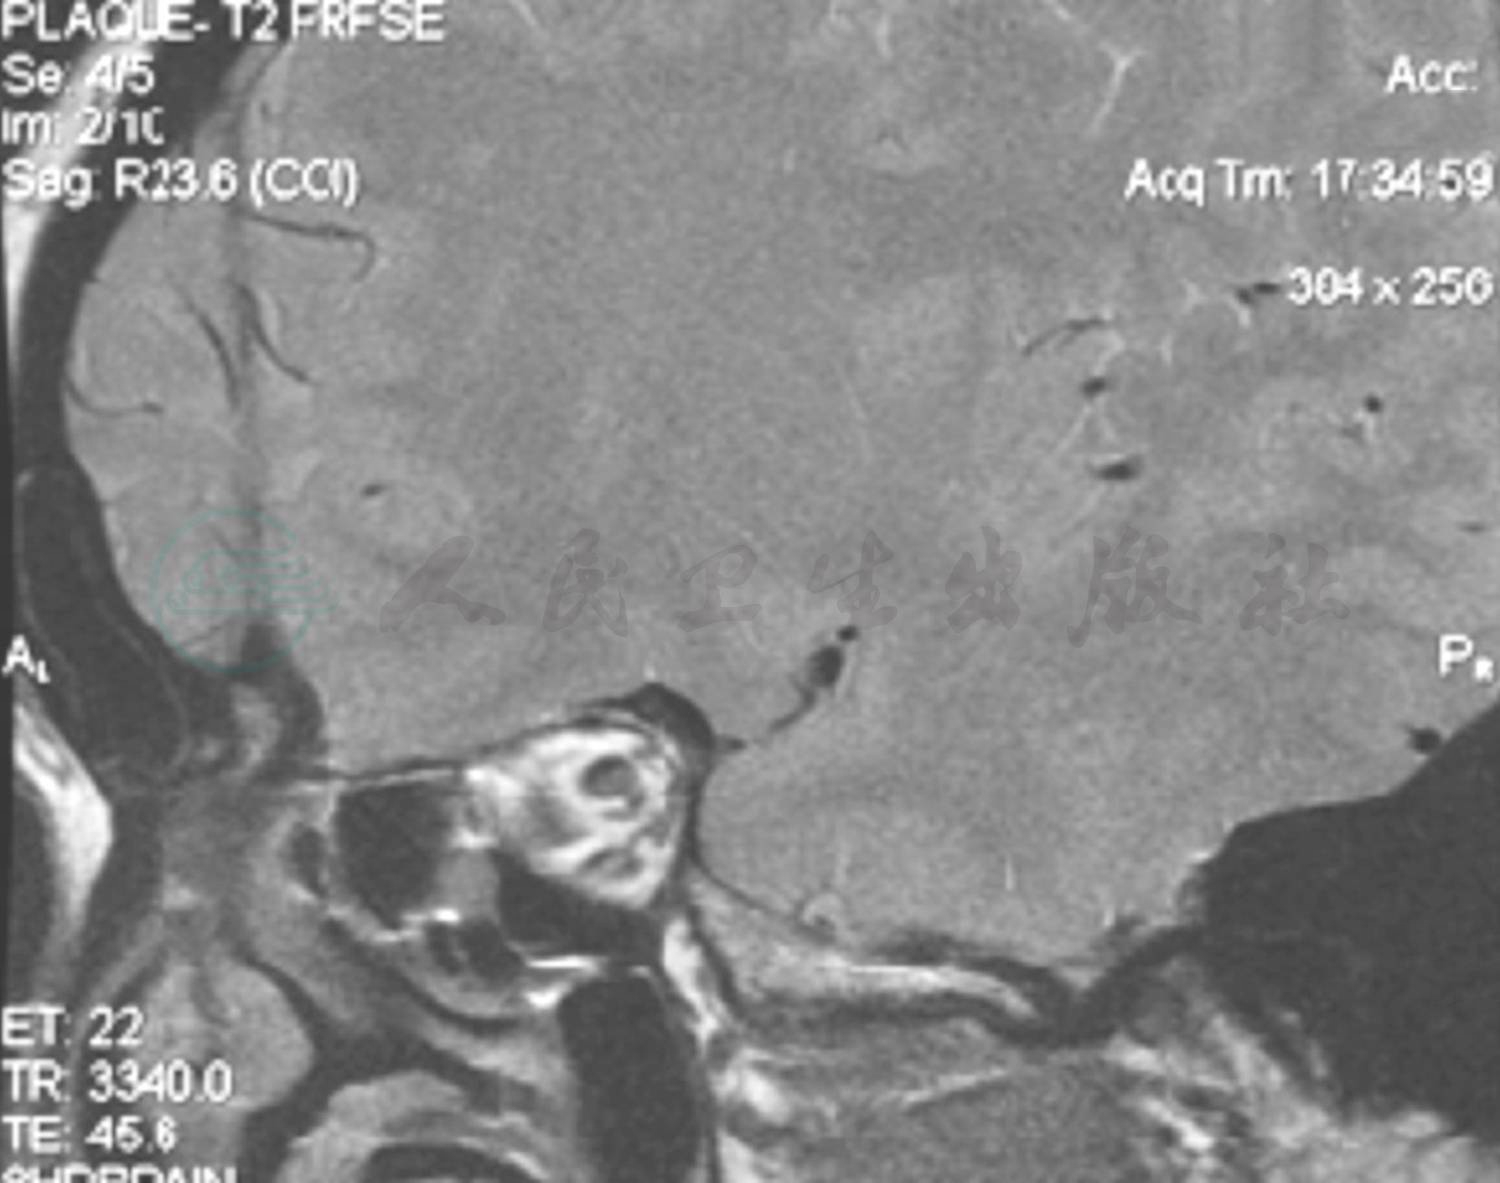

实验室检查血、尿、粪便常规、肝肾功能、血脂、C反应蛋白、红细胞沉降率、甲状腺功能及血清同型半胱氨酸均于正常值范围;血清抗可提取性核抗原(ENA)、抗中性粒细胞胞质抗体(ANCA)、自身抗体及抗核抗体均呈阴性反应。心脏彩色超声扫描、动态心电监测均未见异常变化。颈部血管彩色超声显示双侧颈动脉粥样硬化表现,左侧伴多发硬化斑块形成。入院当日头部弥散加权成像(DWI)扫描显示,右侧基底节区新发脑梗死(图1)。头部MRA检查未见明显异常(图2);高分辨率磁共振大脑中动脉粥样硬化斑块分析显示,左侧大脑中动脉起始段下壁小斑块,右侧大脑中动脉M1段近分叉部前壁可疑小斑块(图2)。

图2 患者右侧大脑中动脉高分辨率磁共振

横断面成像示右侧M1段近分叉部前壁可疑小斑块